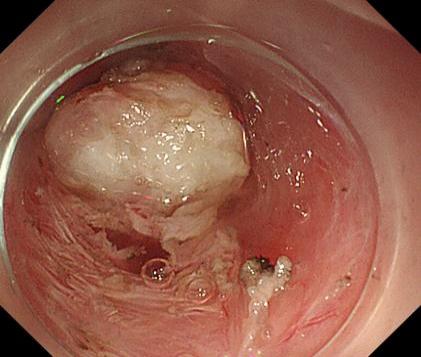

直腸側向發育性腫瘤 內鏡下黏膜下剝離術后創面

內鏡下黏膜剝離術(ESD):治療巨大平坦息肉,早期癌及癌前病變,黏膜下腫瘤等。